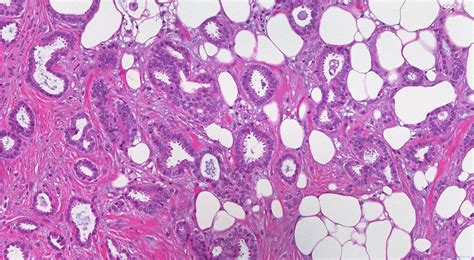

Alright, so what exactly is invasive right breast carcinoma ? Basically, it’s cancer that starts in the right breast and has spread beyond the ducts or lobules where it originated. It’s considered “invasive” because it has broken through the boundaries of the tissue where it began, potentially spreading to other parts of the body. There are various types, with the most common being invasive ductal carcinoma and invasive lobular carcinoma . The former starts in the milk ducts, while the latter begins in the milk-producing lobules. Understanding the type helps doctors determine the best course of treatment. The right breast is simply the location where this process is taking place. This localization is important, as it helps determine the extent of the cancer and guide treatment decisions, like surgery, radiation, and medication. The term “carcinoma” itself refers to a cancer that originates in the epithelial cells – the cells that cover the surfaces of the body, including the breast tissue. This means that when we’re talking about invasive right breast carcinoma , we’re referring to a very specific type of cancer that must be accurately identified and documented for proper care. Guys, remember that early detection is key, and regular screenings are super important. If you feel anything unusual, don’t hesitate to see a doctor! It’s better to be safe than sorry, right?

For invasive carcinoma of the right breast , the code usually starts with the prefix “C50”. Then, there are further codes that specify the exact location within the breast. So, a code might specify the upper-outer quadrant of the right breast, or it might specify the nipple and areola. The codes become more specific as doctors gather more information about the cancer. Another important consideration is the type of cancer. For example, the code will likely specify whether it’s invasive ductal carcinoma or invasive lobular carcinoma. Each type of cancer has its specific codes, which allows for accurate diagnosis. In addition to the location and type, the stage of the cancer is crucial. The stage of the cancer indicates how far the cancer has spread. The codes are grouped by the different stages, from Stage 0 (carcinoma in situ) to Stage IV (metastatic cancer). The specific code used will vary, reflecting the stage of the cancer. The codes also specify whether the cancer has spread to the lymph nodes. Lymph node involvement is a key factor in determining treatment and prognosis. Another thing these codes can tell you is whether the cancer is hormone receptor-positive or HER2-positive. These receptors help determine which treatments will work best.